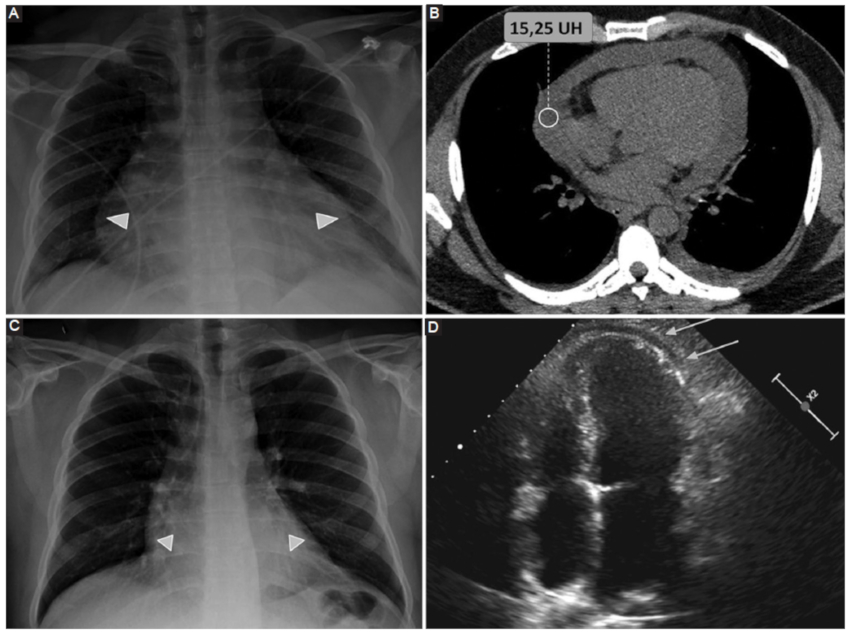

Neumopericardio

Entidad definida por la presencia de aire contenido entre ambas hojas del pericardio. Si bien puede darse de forma idiopática, las causas más frecuentes son postraumática y posquirúrgica (Figs. 3 y 4), secundaria a patología de órganos adyacentes (tubo digestivo o vía aérea) o afecciones del pericardio por gérmenes productores de gas9.

La gravedad del cuadro viene determinada por la posibilidad de desarrollarse un neumopericardio a tensión, el cual genera un síndrome de taponamiento cardiaco con descompensación hemodinámica y requiriendo descompresión de urgencia9.

La TCMC pone en evidencia la presencia de aire contenido entre las hojas del pericardio, aunque en situaciones de urgencia el diagnóstico de taponamiento cardiaco suele ser clínico6.

Pericarditis aguda

Se define como un síndrome pericárdico de tipo inflamatorio que puede darse con o sin DP acompañante («pericarditis seca»)6.

En la mayor parte de los casos se trata en un cuadro idiopático (presumiblemente asociado a infecciones virales), aunque puede manifestarse en el contexto de enfermedades sistémicas como tuberculosis, enfermedades autoinmunes, como hallazgo o complicación posquirúrgica, o asociado a compromiso miocárdico (Figs. 5, 6 y 7) (5,6.

Si bien tradicionalmente se la describe en su forma aguda, también puede darse en curso subagudo o crónico. Los síntomas clásicos de presentación incluyen: dolor torácico agudo, de tipo pleurítico que cambia de intensidad con la posición y signos de fricción pericárdica. Los cambios clásicos en el electrocardiograma (ECG) y la elevación de marcadores serológicos de inflamación apoyan el diagnóstico6.

Entre los signos clásicos de pericarditis aguda por TCMC se describen:

DP: particularmente del tipo exudado, aunque en una minoría de casos puede ser trasudado10.

Engrosamiento del pericardio. Habitualmente las hojas del pericardio miden entre 1,3 y 2,5 mm. Un aumento mayor a 4 mm presenta una alta especificidad para esta patología10.

Realce pericárdico tras la inyección de contraste endovenoso (alta especificidad) (10.

Cabe mencionar que Hammer et al. (10, en su serie de 46 pacientes con diagnóstico de pericarditis aguda, encontraron que el engrosamiento y realce pericárdico valorado por TCMC presenta una sensibilidad del 54-59% y una especificidad del 91-96%10.